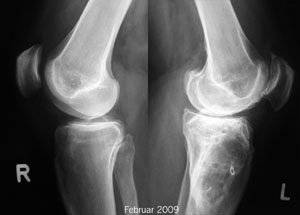

In Zermatt trete ich morgen früh Skitag Nummer 58 dieses Winters an. Gut! Es gibt auch wieder neue Röntgenbilder - auch wenn ich lieber auch links die Qualität des rechten Knies hätte, bin ich ganz zufrieden... kaum Veränderungen.

Röntgenbilder Februar 2009 - Klicken für grössere Fassung